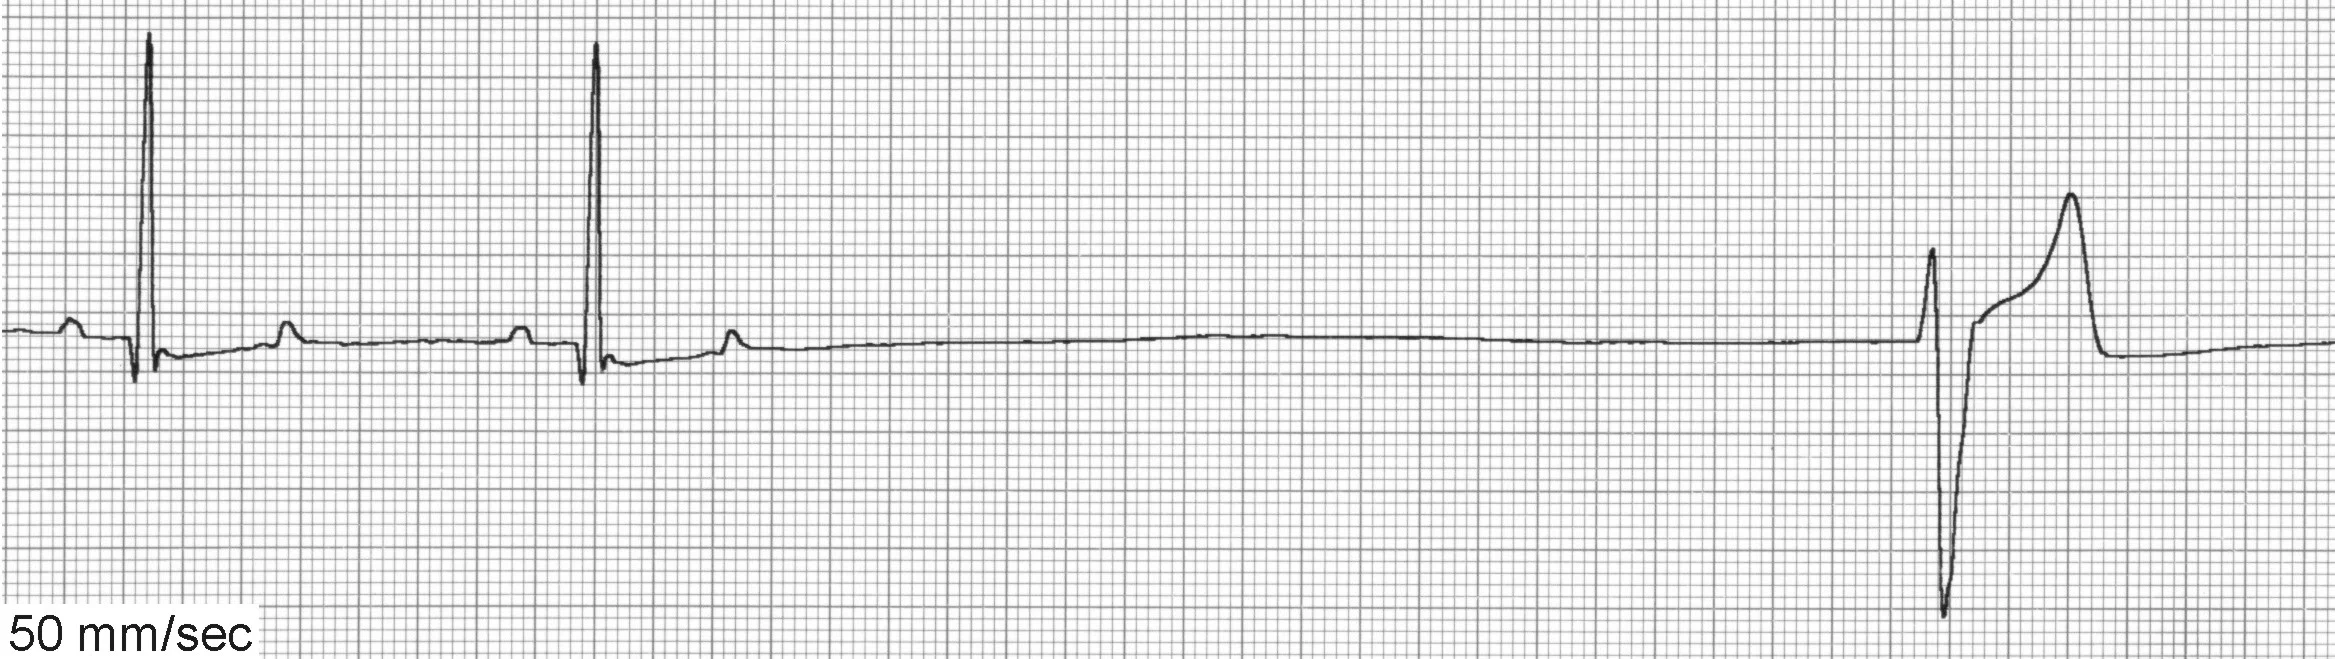

VPCs (Figure 5) can be associated with significant inflammatory, structural, toxic, infiltrative, traumatic, or ischemic heart disease. VPCs are also common in patients with noncardiac disease (eg, gastric dilatation-volvulus [GDV], splenic disease/surgery, hyperthyroidism, sepsis, anemia, hypoxia, myocarditis/infectious disease, coagulopathies). Patients with elevated sympathetic tone from extreme excitement or pain may also display VPCs, as well as drug therapy with digoxin, anesthetics (especially short-acting thiobarbiturates), and catecholamines.

ECG of ventricular premature complexes

ECG of ventricular escape beats

VPCs generally occur <1 R-R interval from the preceding sinus beat (vs ventricular escape beats [Figure 5B] that generally occur >2 R-R intervals from the preceding sinus beat) and are not associated with preceding P waves. Care must be taken to exclude these arrhythmias from sinus rhythm with chamber enlargement patterns or sinus rhythm with conduction disturbances.

The decision to treat VPCs can be difficult. Frequent and multiform VPCs in the presence of underlying heart disease, especially with clinical signs, will necessitate treatment. Infrequent, uniform VPCs without clinical signs or heart disease uncommonly require treatment. Treatment for VPCs secondary to underlying metabolic disease is usually not indicated and therapy should instead be aimed at correcting the underlying condition.